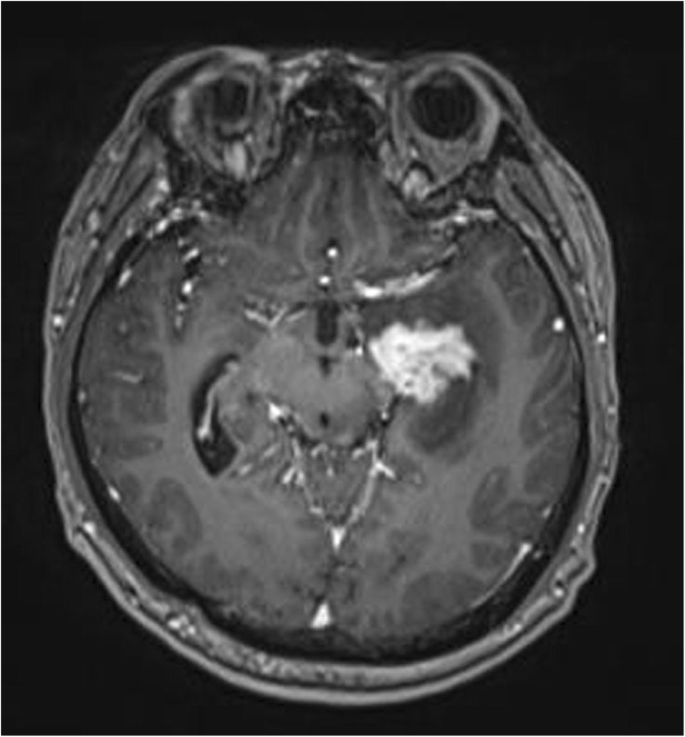

A typical case: a 38-year-old right-handed male was hospitalized mainly due to progressive left limb fatigue for more than 3 months and aggravated nearly 1 week. Physical examination showed a poor coordinate movement of the left limbs. Enhanced MRI and magnetic resonance spectroscopy imaging indicated multiple intracranial neoplastic lesions, probably lymphoma (Figs. 1, 2, and 3). PETCT scan showed a high-level metabolism in the lesion areas (Figs. 4 and 5). MRI was performed to locate the lesions after preoperative installation of the Leksell headgear (Fig. 6). Preoperative surgical plan was conducted at the BrainLab workstation. Multi-image fusion-guided stereotactic surgery was performed for intracranial lesion biopsy. Multi-image fusion and three-dimensional reconstruction showed the relationship between lesions and fiber bundles as well as intracranial vessels (Fig. 7). Based on the biopsy target and the path, the biopsy needle was placed into the lesion center, and the specimen was obtained after multidirectional suction at a single target. After surgery, the patient underwent an iMRI scan (Fig. 8). Intraoperative MRI confirmed no secondary bleeding. In addition, the puncture orbit was consistent with the preoperative planned orbit with no deviation, and the target lesion was weakened and the specimen was successfully obtained (Fig. 9). Postoperative pathological analysis revealed a non-Hodgkin lymphoma and diffuse large B cell lymphoma. Immunohistochemical staining showed CD3(−), CD20(+), PAX5(+), Ki-67 (about 70%+), CD10(−), Bcl-6(+), Mum-1(+), BCL2 (about 80%+), C-MYC (about 40%+), CD5(+), CD21(−), CyclinD1(−), CK(−), and GFAP(−) (Fig. 10). After the operation, the patient's symptoms were not aggravated, and had no other neurological dysfunction.